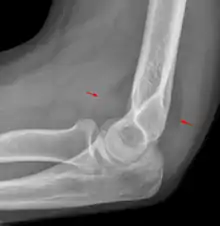

علامة الوسادة الدهنية (بالإنجليزية: Fat pad sign) أو علامة الشراع (بالإنجليزية: Sail sign) هي علامة طبية تظهر في الأشعة المقطعية وتشير إلى كسر عظم مخفي. شكلة على شكل شراع.[1] سبب هذه العلامة هو إزاحة الوسادة الدهنية المحيطة بمفصل المرفق. قد تظهر علامة أمامية أو علامة خلفية أو تظهر كلتا العلامتين.

تظهر علامة الوسادة الدهنية الخلفية في حالة الكسر اللقمي لعظم العضد. أما عند البالغين، فتظهر في حالة كسر رأس الكعبرة. تحدث علامة الوسادة الدهنية في الكسور التي تحدث داخل المفاصل فقط.

يمكن ضغط الوسادة الدهنية الخلفية في الحفرة الزجية بواسطة الضغط على وتر العضلة ثلاثية الرؤوس العضدية، وبذا ستكون غير مرئية لتصوير جانبي للمرفق بالأشعة.[3] عندما يكون هناك كسر في طرف عظم العضد أو وجود أي مرض يصيب المرفق أو التهاب يحدث حول الغشاء الزليلي، فهذه ستزيح الوسادة الدهنية عن مكانها الطبيعي. تعد علامة الوسادة الدهنية الخلفية العلامة الواضحة الوحيدة لكسر، ولا سيما عند الأطفال.

علامة الوسادة الدهنية الأمامية وكذلك الوسادة الدهنية الخلفية لطفل يعاني من كسر فوق اللقمة